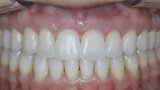

New Age orthodontics and orthopaedics with temporary anchorage devices